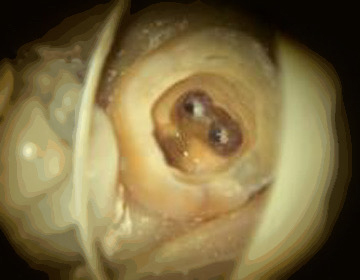

根管治療は、噛み合わせを変化させること無く、マイクロスコープを用いた目視確認による治療技術で根管内の感染、異物はもちろん、中に溜まったエネルギーを適切に取り除くことで、歯だけでなく顎関節症の原因である顎の痛みや筋肉の緊張を取り除きます。

根管治療では、 汚染された根管 内を完全に洗浄し、痛みを除去し、

違和感なく自然に噛めるまで確実に回復する治療を行います。

CT撮影、麻酔後、ラバーダム防湿を行って根管治療を開始します。

噛み合わせが狂わないよう、歯の周りは残して根管治療を行います。

根管内の汚染物質、汚染資質を取り除き、痛みが取れるまで、徹底的に洗浄します。根管内に貯まったエネルギー調整も同時に行います。

複雑な根の細部にまで材料が入るように特殊な装置で根管を行います。

痛み、レントゲン検査による治療結果の判定。